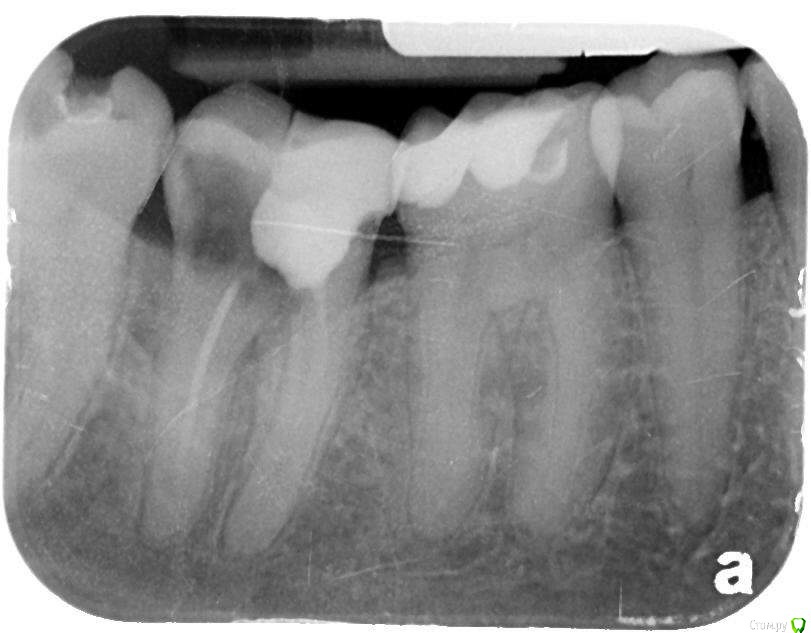

Javor Опубликовано 26 августа, 2015 Поделиться Опубликовано 26 августа, 2015 Подскажите пожалуйста можно ли сохранить зуб, Мой стоматолог сказал, что зуб сломался и нужно его удалить. Он не уточнил как именно сломался, Это случилось месяцев 5 назад. Сначала зуб болел, а потом перестал, Боюсь на нем жевать, но и удалять так не хочется. Высылаю снимок. Заранее спасибо, 1 Ссылка на комментарий

колесников Опубликовано 26 августа, 2015 Поделиться Опубликовано 26 августа, 2015 тут и думать нечего. перфорация в бифуркации и разрушение ниже уровня десневого края + облитерированые каналы. не надо бегать по врачам и вкладывать в него деньги. ни один здравомыслящий ортопед не возьмёт этот зуб под вкладку. удаляйте и одномоментно ставьте имплант. будете ещё ждать,получите потерю кости по высоте и проблемы с протезированием на импланте. 2 1 Ссылка на комментарий